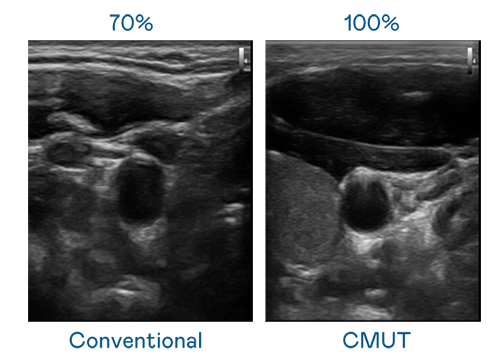

CMUT 技术是一种用电容式微机电元件来产生超音波讯号的技术。与传统 PZT 压电式技术相比,CMUT 频宽增加 30%,更宽频的超音波讯号让影像解析度大幅提升,是实现高影像品质医疗超音波扫描、促进精准医疗发展的关键技术。

大频宽带来超清晰影像

超音波影像的解析度高低,首先取决于探头能发出的讯号频宽。天博体育 CMUT 可提供高清晰的超音波讯号,提供高频宽、高灵敏度、影像纹理细节更高的超音波影像,协助医护人员缩短影像判读时间及利用精准的医疗影像进行诊断。